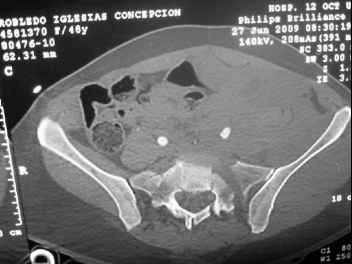

I'm posting this case on behalf of Dr. Pedro Caba, he is unable to post but able to read. 41 yo female , fall from 10 meters five days ago. Hemodynamically unstable on admission treated by angio and embolization and skeletal traction, with no external support. No associated injuries. Based on CT scan the pt has a both column fracture with conminuted dome and displaced anterior column and a sacral Denis 1 fracture with a displaced left ala. I think the best approach for the acetabular fracture is ilioinguinal with Smith-Petersen extension but don't know exactly the sequence . Will you start with the sacral fracture? Which technique? Thanks in advance Pedro Caba Unidad de Trauma Hospital 12 de Octubre Madrid Spain

The soft tissues are also in mild condition, buttock hematoma and probably a Morel-Lavalle. I send some more CT images. There are some conminution in the posterior column (I don’t have images now). The patient is scheduled for surgery next Monday. The plan is percutaneous sacral fixation and then ilioinguinal approach .

This complex and displaced sacral injury is likely an H pattern...2 hemipelvic components, an upper sacral component which remains attached to the lumbar spine, and a caudal sacral component...there are typically anterior ring injuries as well...in this patient's example, the left sided acetabulum also has been exploded.

The hemipelvic components' displacements depend on their instability...this patient's left side seems to be the worst.